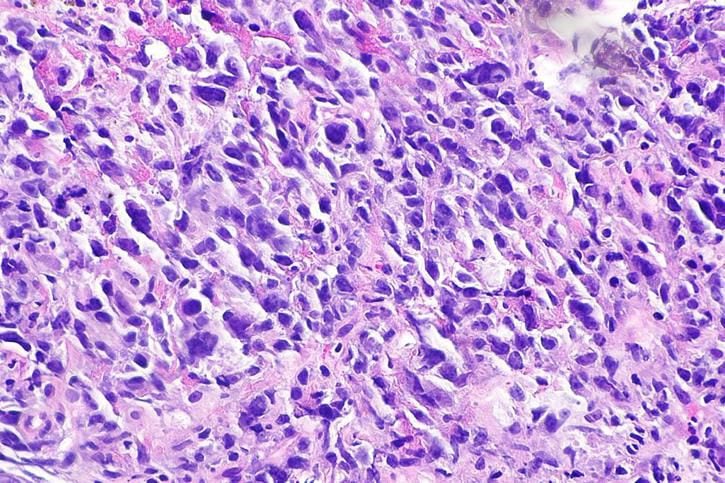

El linfoma es un tipo cáncer que se origina en el linfocito, que es una célula que forma parte del sistema inmunológico, circula en la sangre y reside en el ganglio linfático, en el bazo y en la médula ósea.

Los linfomas no Hodgkin son los más comunes y se los suele dividir en linfomas B o T, según el linfocito que le dio origen. “A su vez, pueden clasificarse según el comportamiento clínico en indolentes y agresivos. Los más frecuentes son el linfoma difuso de células grandes B, que es de comportamiento agresivo y el linfoma folicular de comportamiento indolente. Los de tipo agresivo crecen rápidamente y dan síntomas en forma más precoz por lo que se pueden encontrar en estadíos más tempranos y son potencialmente curables con el tratamiento”, indicó.

La hematóloga del IAF remarcó, además, la importancia de que un anátomo patólogo especializado en hematopatología evalúe la muestra de la biopsia para diagnosticar con certeza el subtipo de linfoma. Adicionalmente, se pueden tomar muestras para enviar a citometría de flujo que en algunos casos puede informar rápidamente en 24 o 48 horas si las células observadas en el material tienen marcadores compatibles con linfoma; y también extraer muestras para la realización estudios genéticos y moleculares.